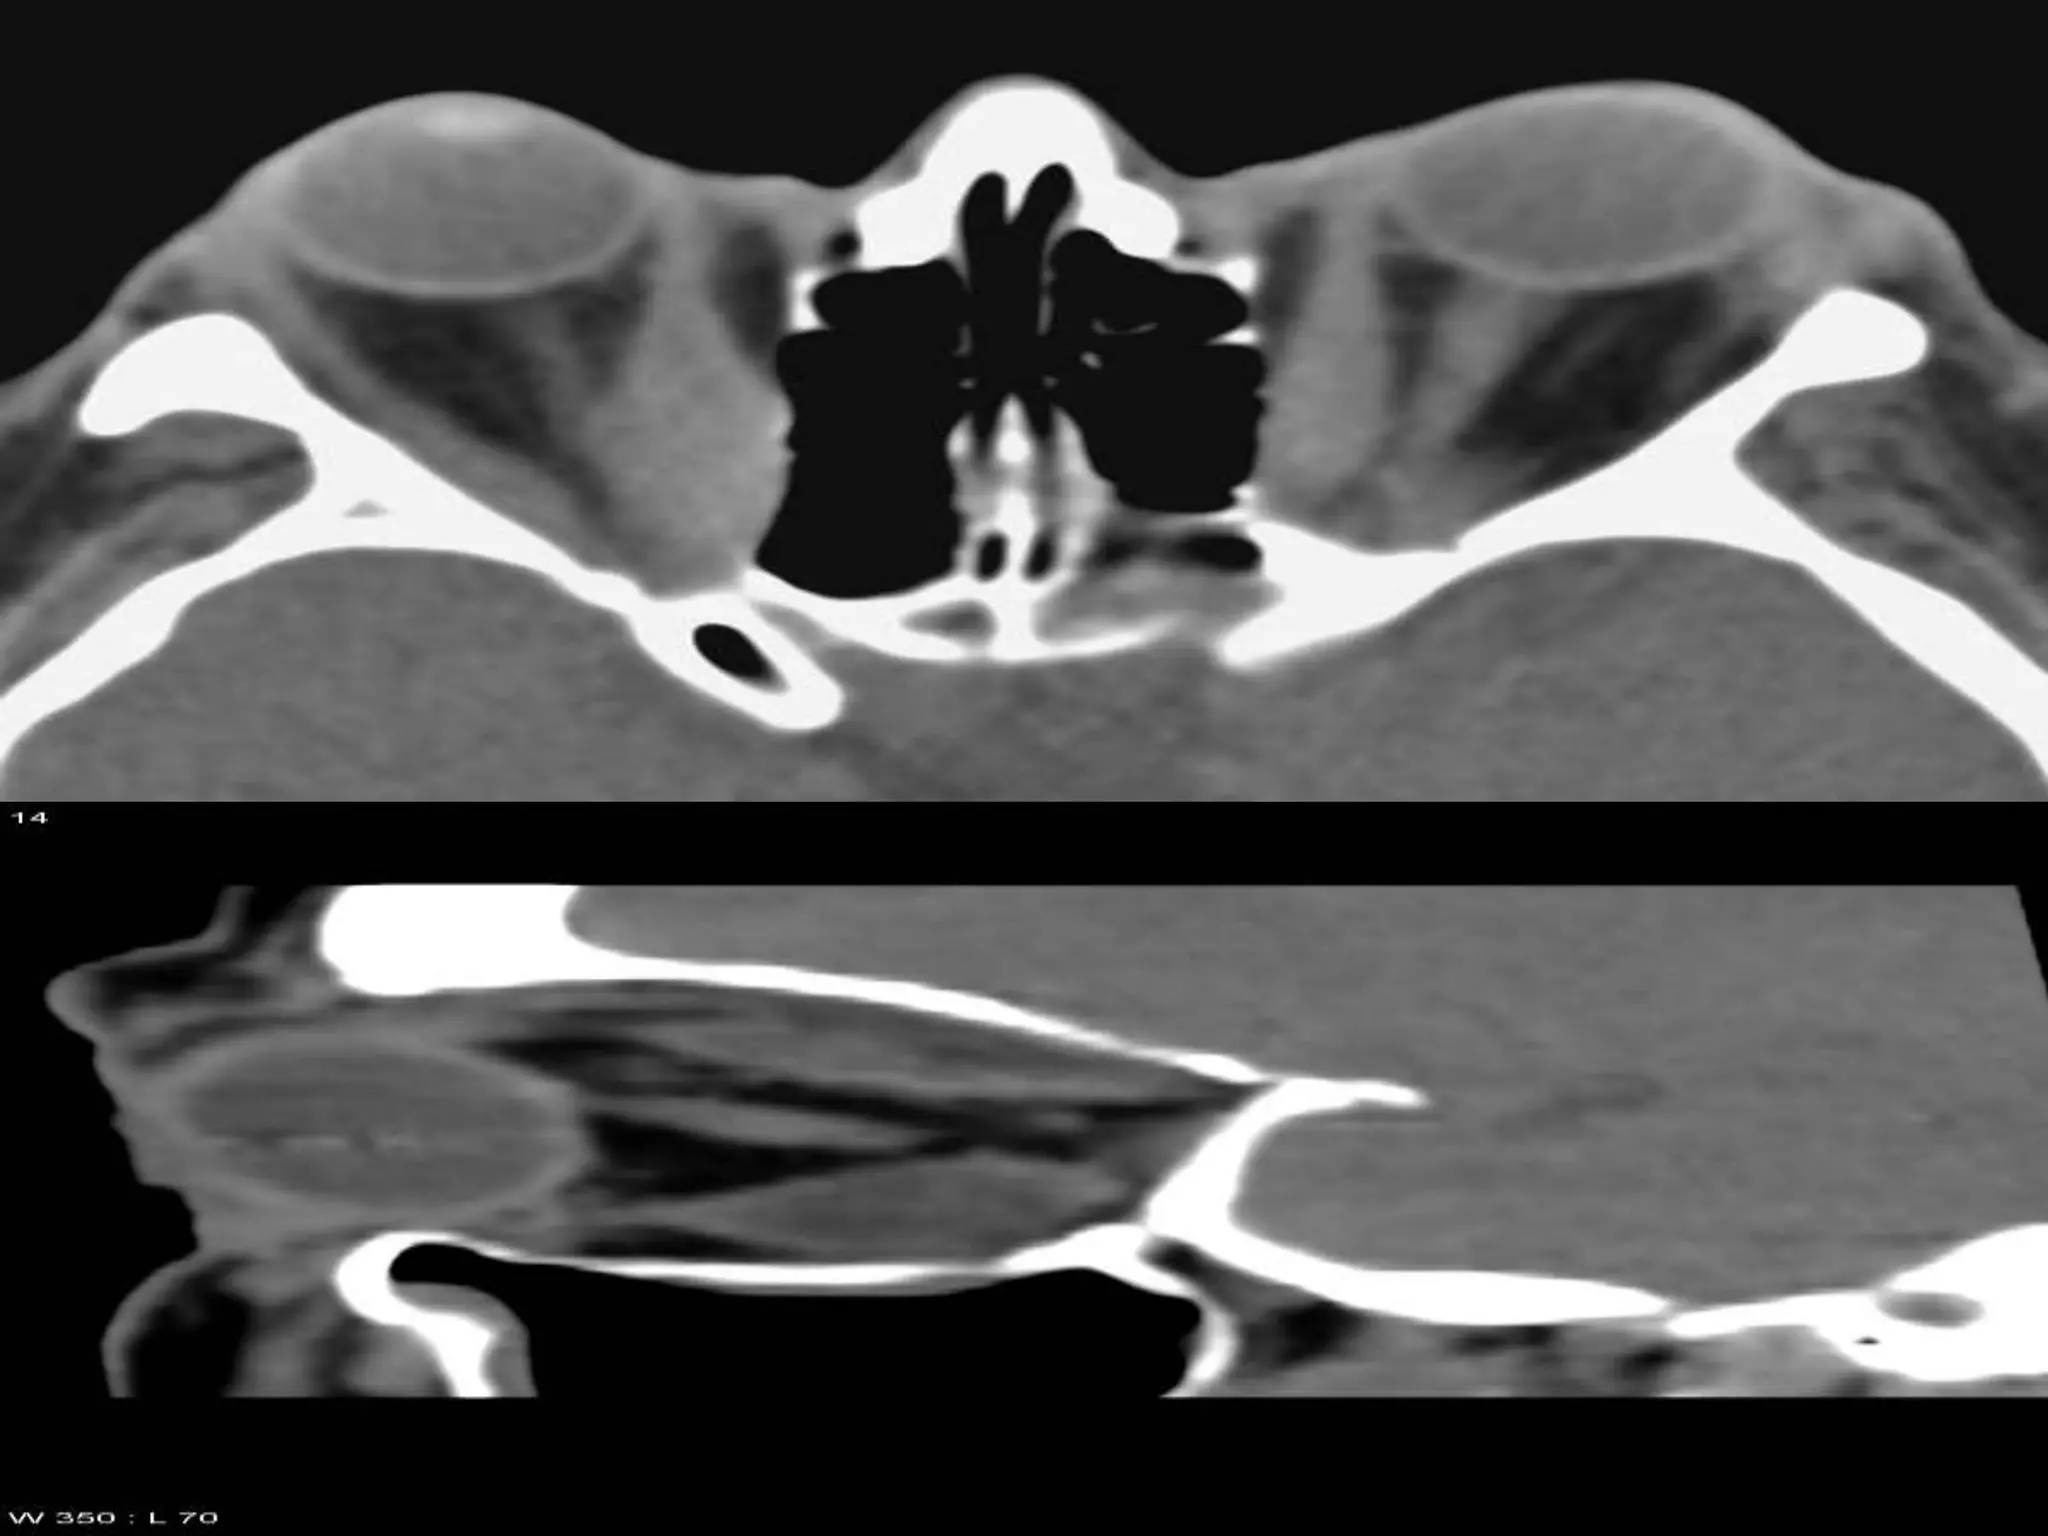

MEASURING PROPTOSIS ON A CT

SCAN

HILAL AND TROKEL METHOD:

-In a mid axial CT scan image,a baseline between the tips of lateral

orbital rims is drawn.

-a perpendicular from each corneal apex to this line is dropped &

measured to scale.

if each line > 21mm

or indicates abnormality.

if asymmetry >2mm b/w two

Quick clinical assessment of proptosis: